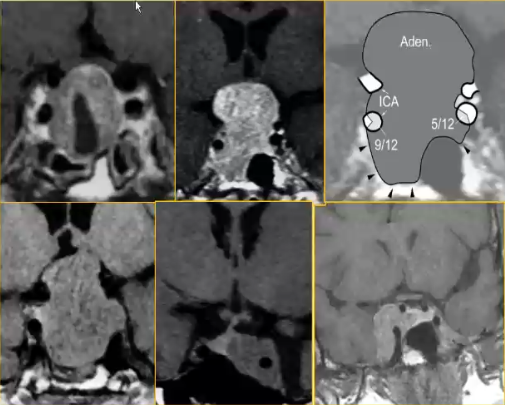

垂体肿瘤海绵窦侵犯

√海绵窦侵犯与颈内动脉接触的范围有关:

√肯定侵犯:≥67%(PPV100%)

√很可能侵犯:海绵窦结构显示不清(PPV95%)或肿瘤超过上外侧(85%)

√无侵犯:≤25%或肿瘤不超过上外侧